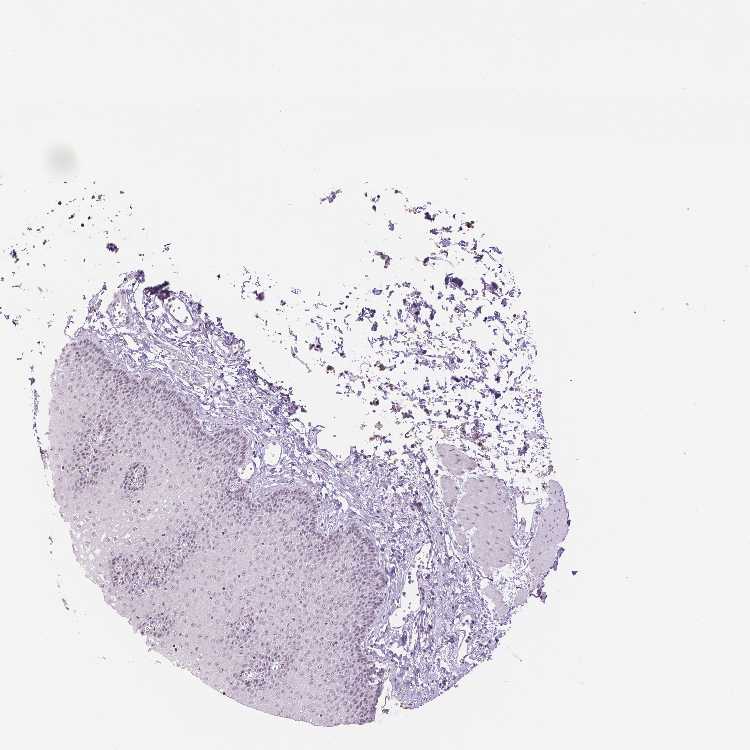

ESOPHAGUS - Antibody stainingi

Antibody staining in the annotated cell types in the current human tissue is reported as not detected, low, medium, or high, based on conventional immunohistochemistry profiling in selected tissues. This score is based on the combination of the staining intensity and fraction of stained cells.

Each image is clickable and will lead to virtual microscopy that enables deeper exploration of all samples and also displays staining intensity scores, fraction scores and subcellular localization as well as patient and tissue information for each sample.

Antibody HPA044171Antibody HPA050400

Squamous epithelial cells LowLow